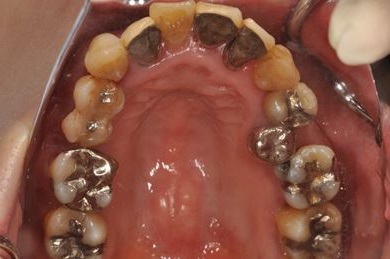

インプラントの症例写真 IMPLANT

骨再生スピードインプラント治療+セラミック治療

| 性別/年齢 | 女性 / 43歳 | ||||||||||||||||||||||||||||||||

| 主訴 | 骨が薄いが、インプラント治療を希望。 | ||||||||||||||||||||||||||||||||

| 治療内容 | インプラント9本(抜歯即日スピードインプラント、ソケットリフト、テンポラリーインプラント+仮歯)、メタルボンドセラミッククラウン18本、メタルボンドセラミックブリッジ6本(メタルボンド用土台6本)、遊離歯肉移植術 | ||||||||||||||||||||||||||||||||